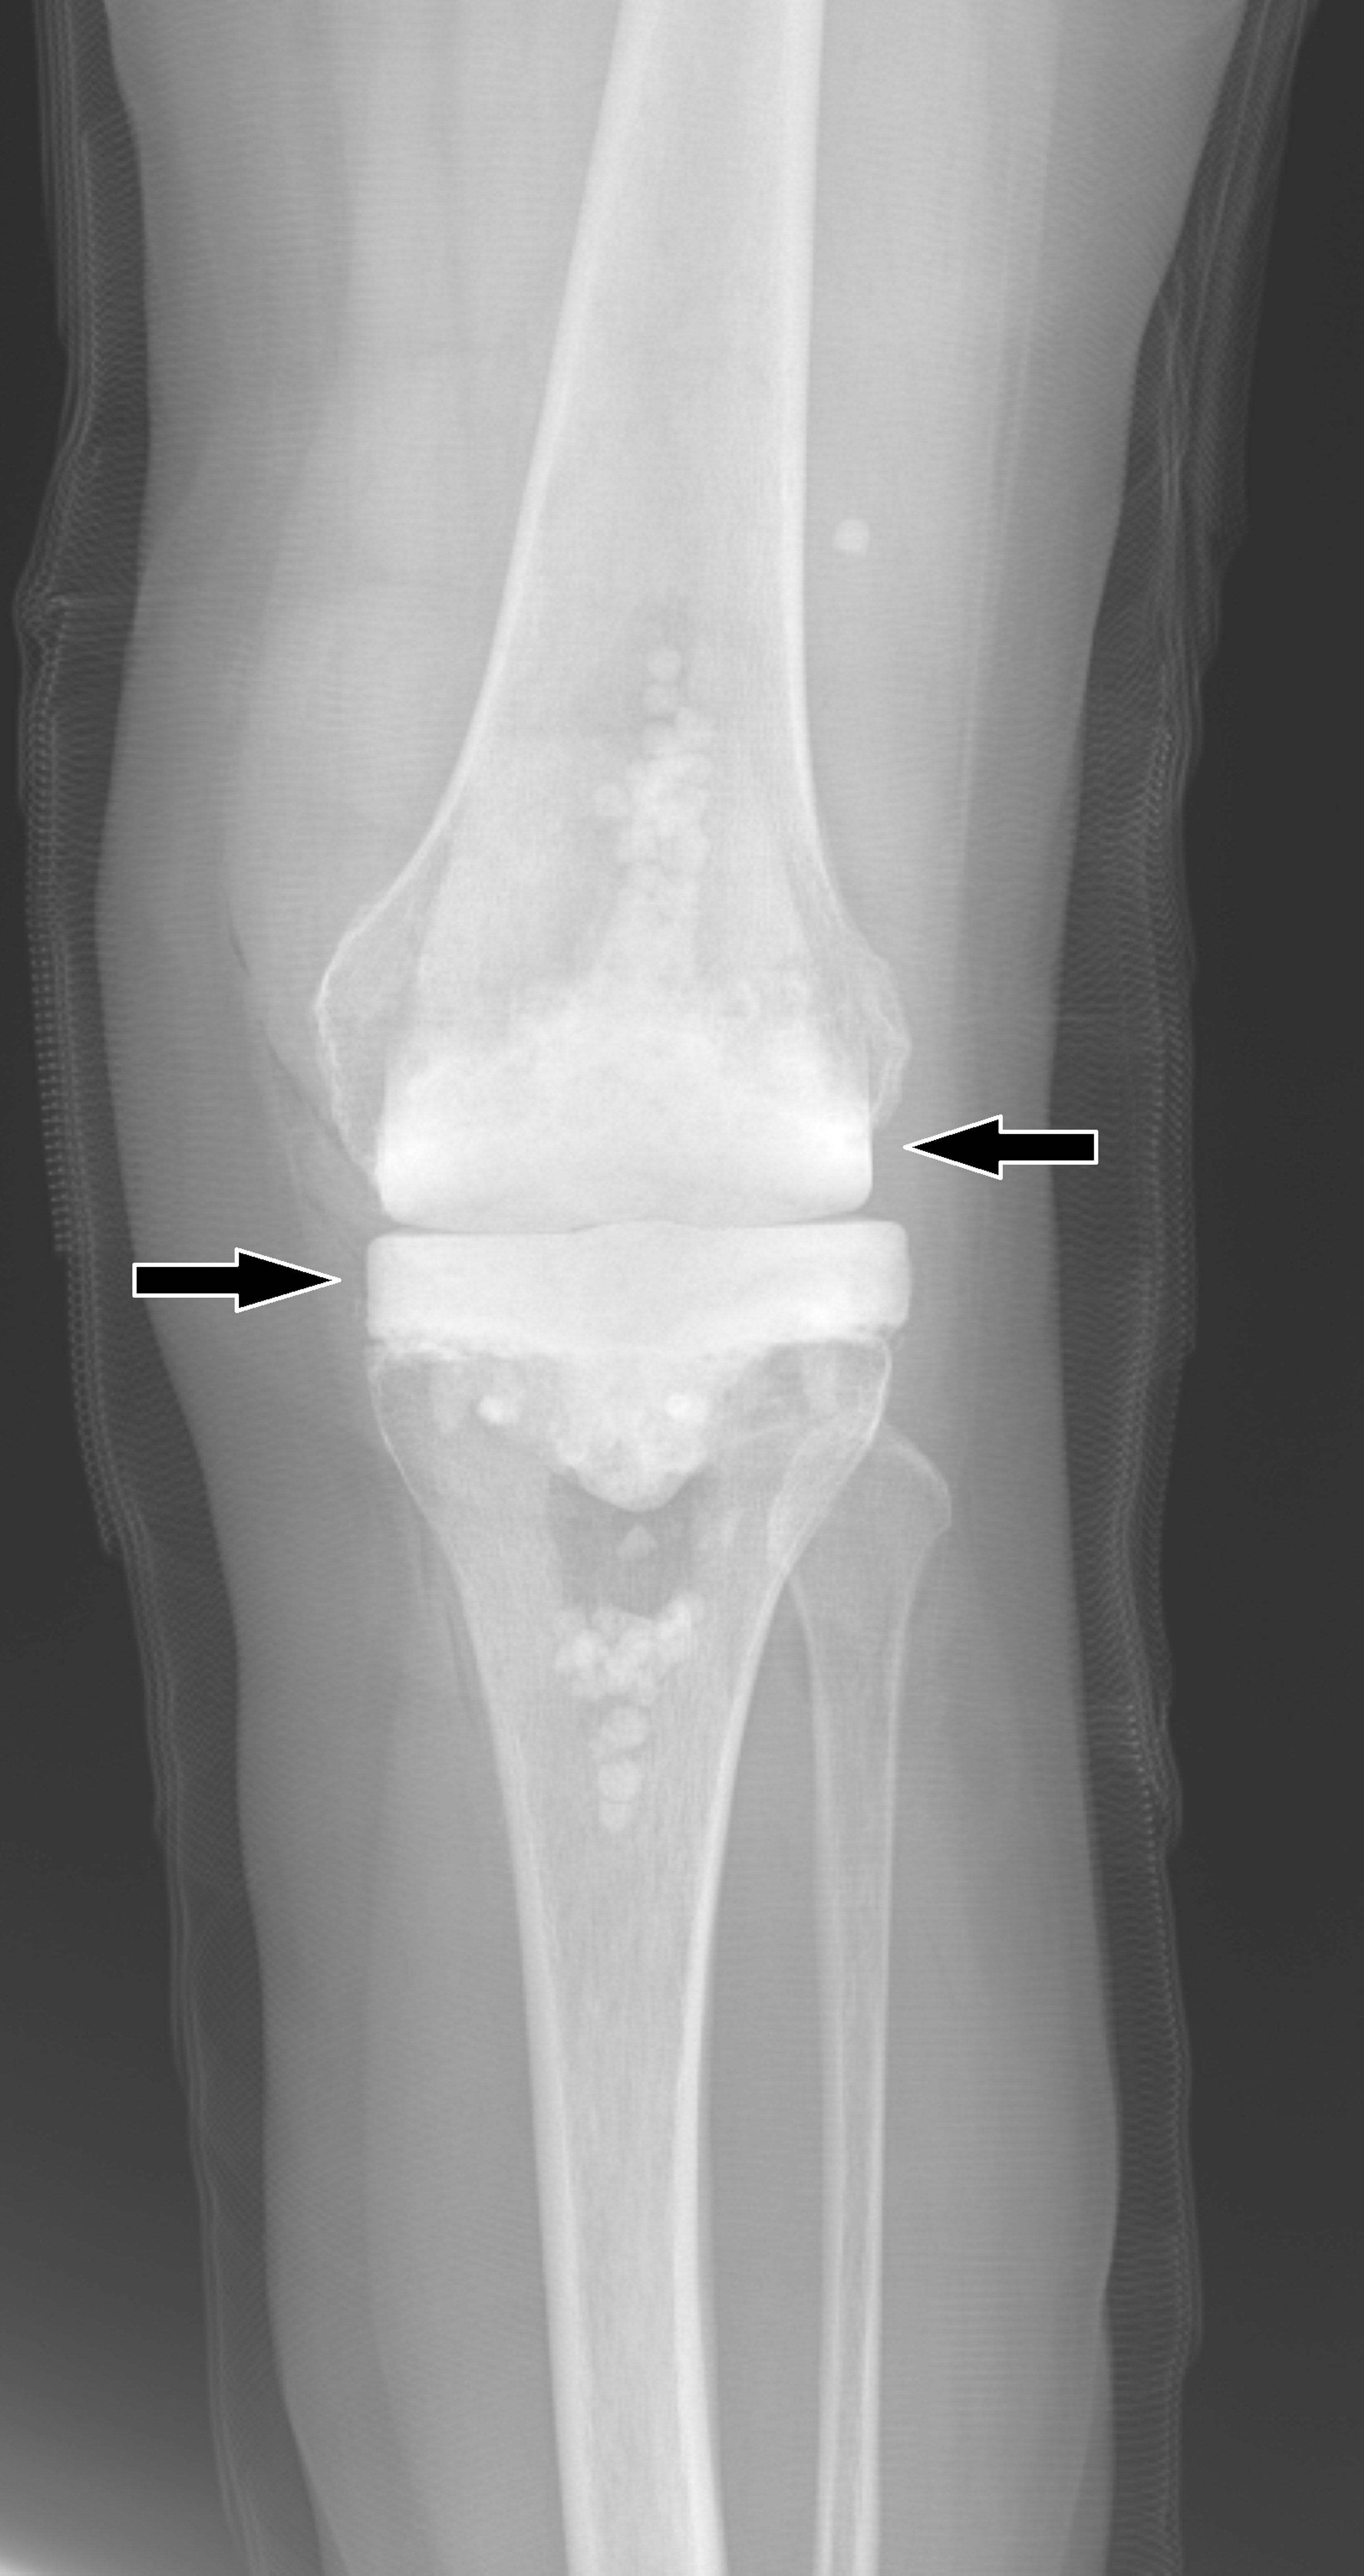

Infected Total Knee Replacement Cement Spacer Musculoskeletal Key Replacing Spacer Total Knee Replacement Replacing a spacer is a much less severe operation than having a total knee replacement. Yes, your knee will have to be. When a total knee replacement prosthesis fails, a second knee surgery is required. If your knee replacement fails, your doctor may recommend that you have a second surgery — revision total knee replacement. Partial or total knee replacement. Replacing Spacer Total Knee Replacement.